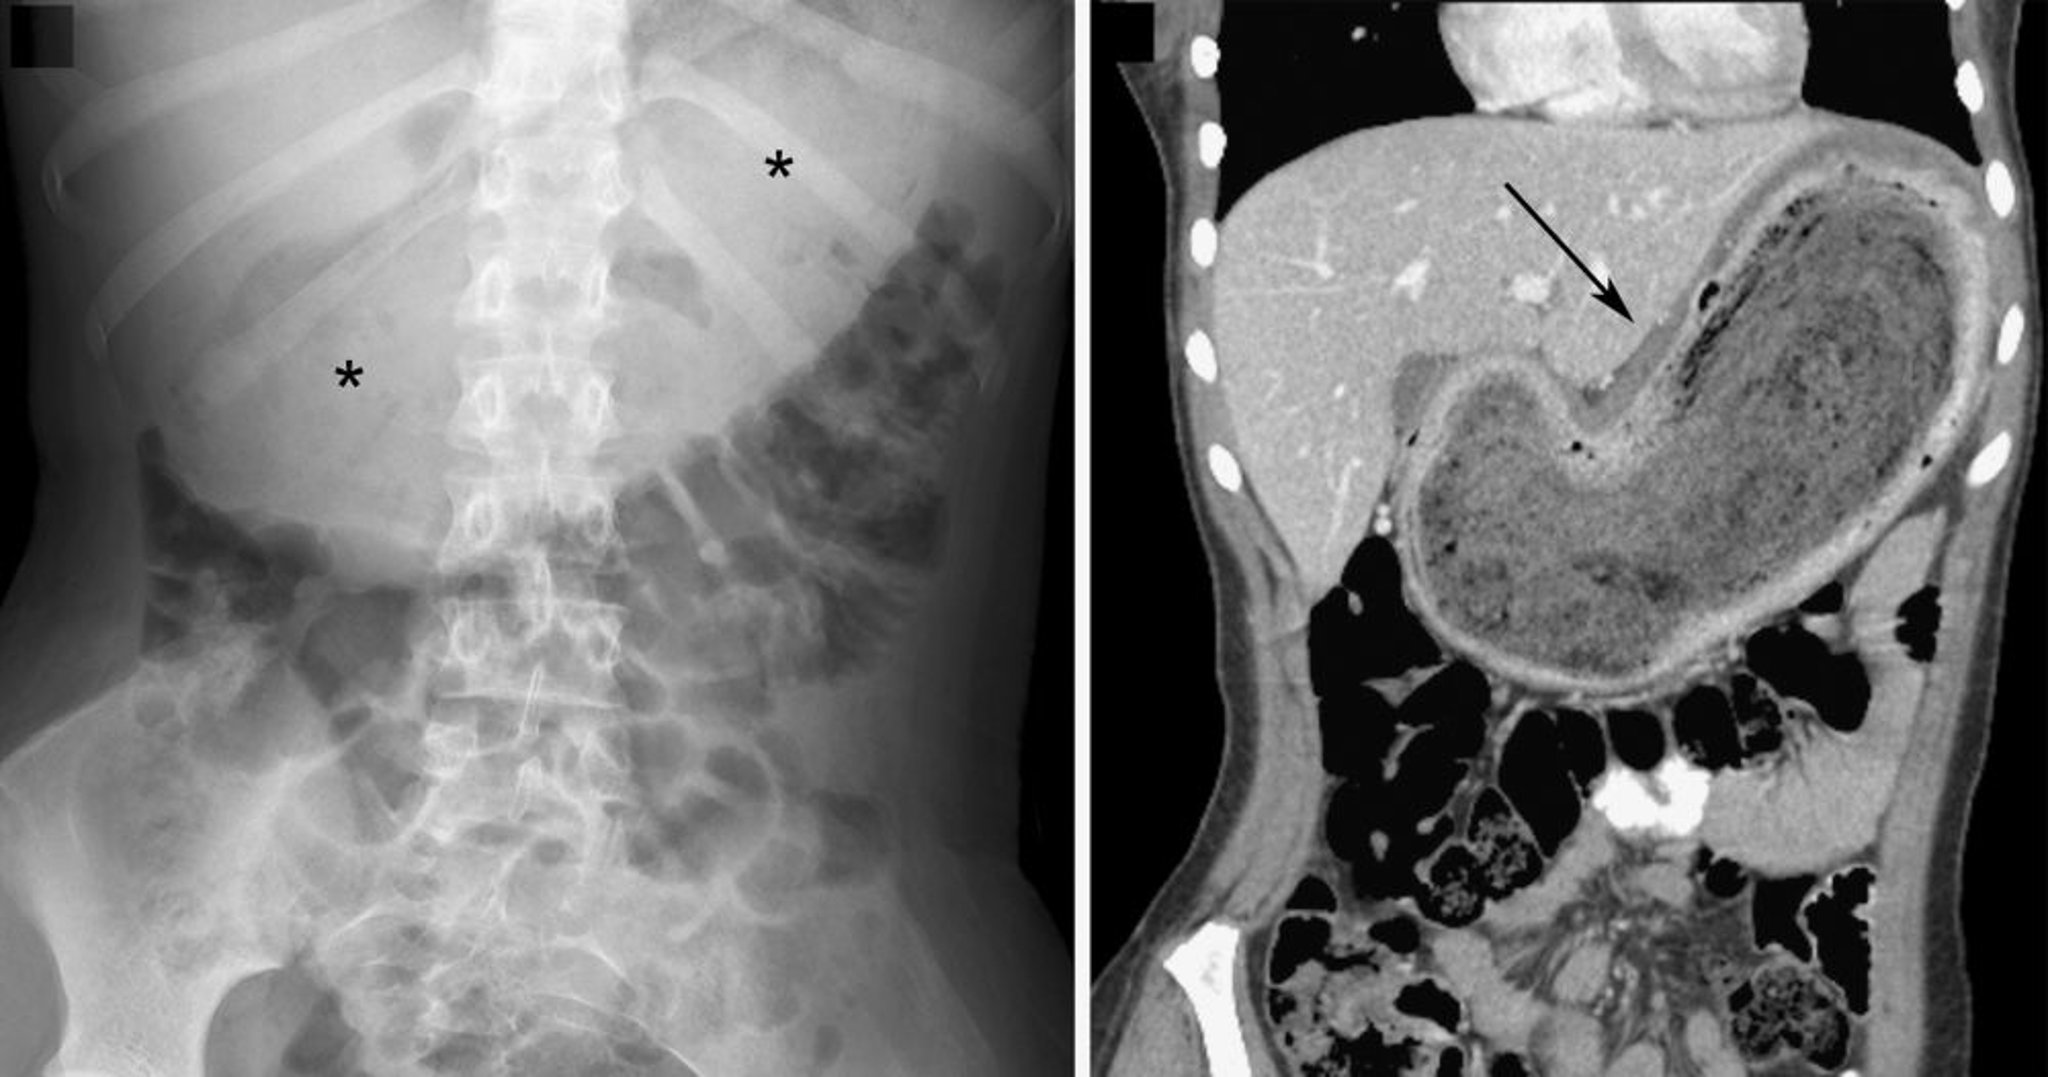

Bezoar (reperti radiografici con imaging)

Nell'immagine radiografica a sinistra, il bezoario è indicato dalla grande massa di tessuti molli nella linea mediana dell'addome superiore con un aspetto variegato di gas intralesionale (asterischi). Nell'immagine ottenuta mediante scansione TC coronale a destra, il bezoario è indicato dalla massa eterogenea (freccia). In entrambe le immagini, vi è uno spostamento inferiore delle anse intestinali.